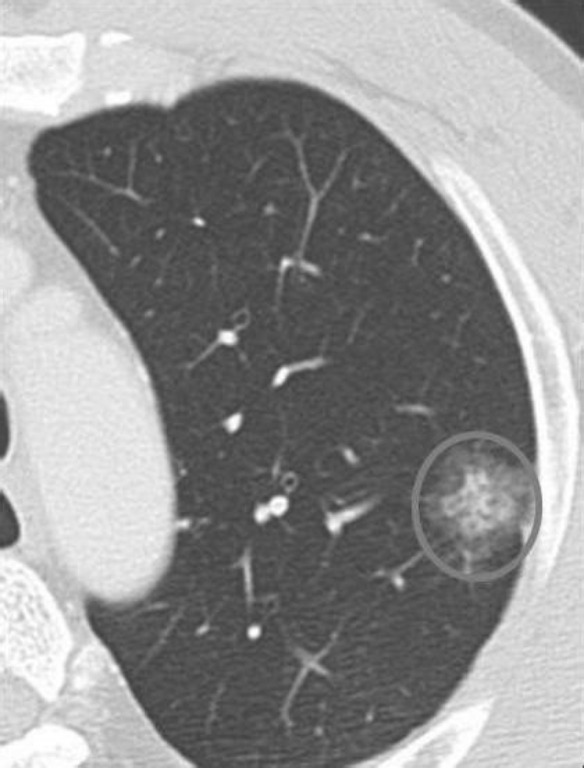

由於低劑量輻射胸部電腦斷層可以偵測到0.2公分大小的病灶,然而並非所有的肺結節都是惡性腫瘤,也可能是肺部感染留下的疤痕或纖維化等良性組織。這些微小的肺結節在診斷預後上造成困難,因此醫師常會建議以電腦斷層追蹤,追蹤之間隔則需視肺結節的大小、質地、形狀、有無鈣化而定。

肺結節的質地可分為純毛玻璃狀、部分實質性、完全實質性。純毛玻璃狀病灶很有可能是原位肺腺癌或是癌症前期病灶-非典型腺瘤增生。

若肺結節為純毛玻璃狀且大於0.8公分,或是為部分/完全實質性,則會建議手術切除;若小於0.8公分的純毛玻璃狀病灶,則建議3個月後再追蹤電腦斷層,2次追蹤後病灶若無縮小情況,則考慮手術。若小於0.5公分的純毛玻璃狀病灶,則半年後再追蹤電腦斷層,無明顯變化再拉長追蹤期間。若追蹤期間出現實質化之變化,則建議手術切除。

B. 部分實質性毛玻璃狀肺結節